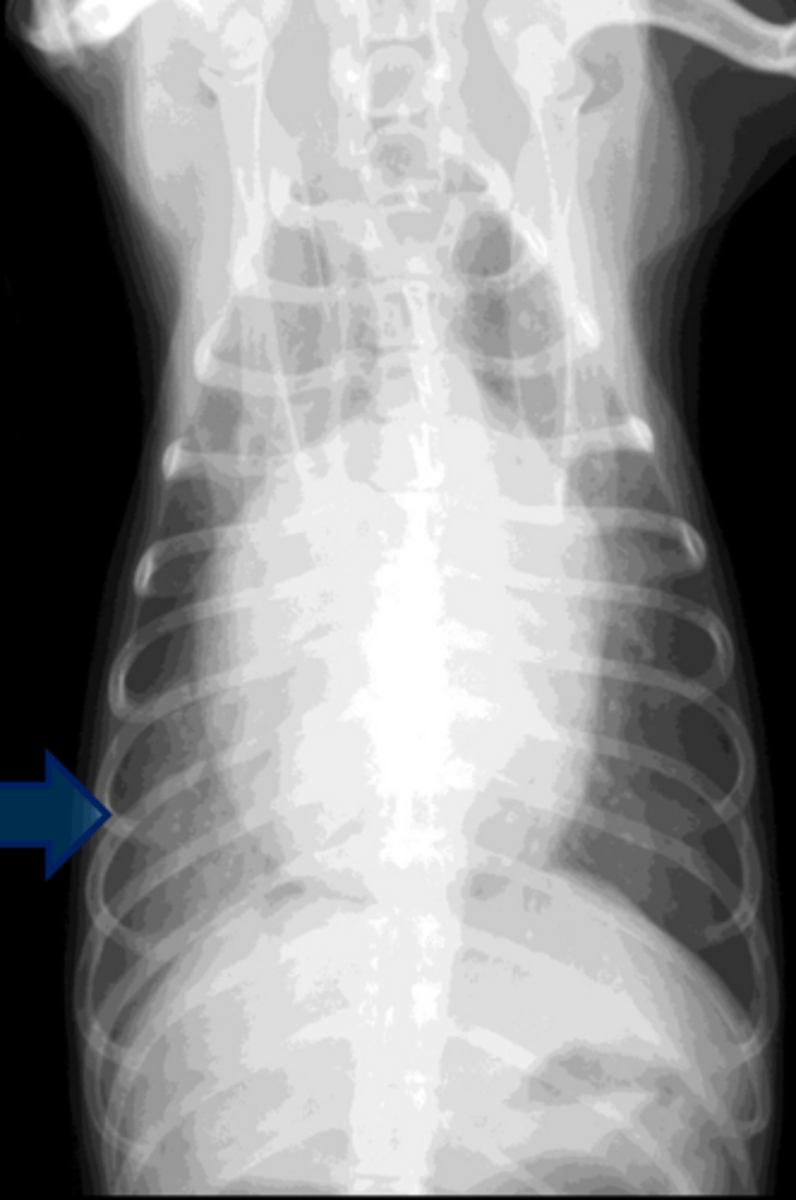

DVD

-Stage B2

-Can see vessels and lungs clear (not CHF yet)

-Bronchus bowing so LA enlargement

What is the dx?